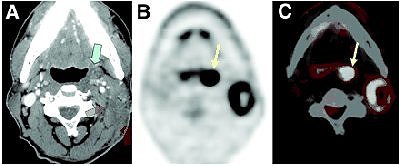

| HNSCC metastasis from unknown primary tumor. Patient had enlarging 3-cm left neck mass felt on physical examination. (A) Contrast-enhanced CT depicted space-occupying lesion (green arrows) in left neck. Biopsy of lesion was obtained by fine-needle aspiration, and lesion proved to be lymph node metastatic squamous cell carcinoma. There was no clear evidence of primary tumor except for subtle asymmetry at left tonsillar fossa (blue arrow) that was of uncertain significance. F-18 FDG PET (B) and fusion PET/CT (C) clearly identified primary tumor at left tonsillar fossa (yellow arrows); finding was confirmed by endoscopic biopsy. Quon A, Fischbein NJ, Ross McDougall IR, Le Q, Loo Jr BW, Pinto H, Kaplan MJ, "Clinical Role of 18F-FDG PET/CT in the Management of Squamous Cell Carcinoma of the Head and Neck and Thyroid Carcinoma" (Journal of Nuclear Medicine, Vol. 48, No. 1 (Suppl): 58S-67S). Reprinted by permission of the Society of Nuclear Medicine. |